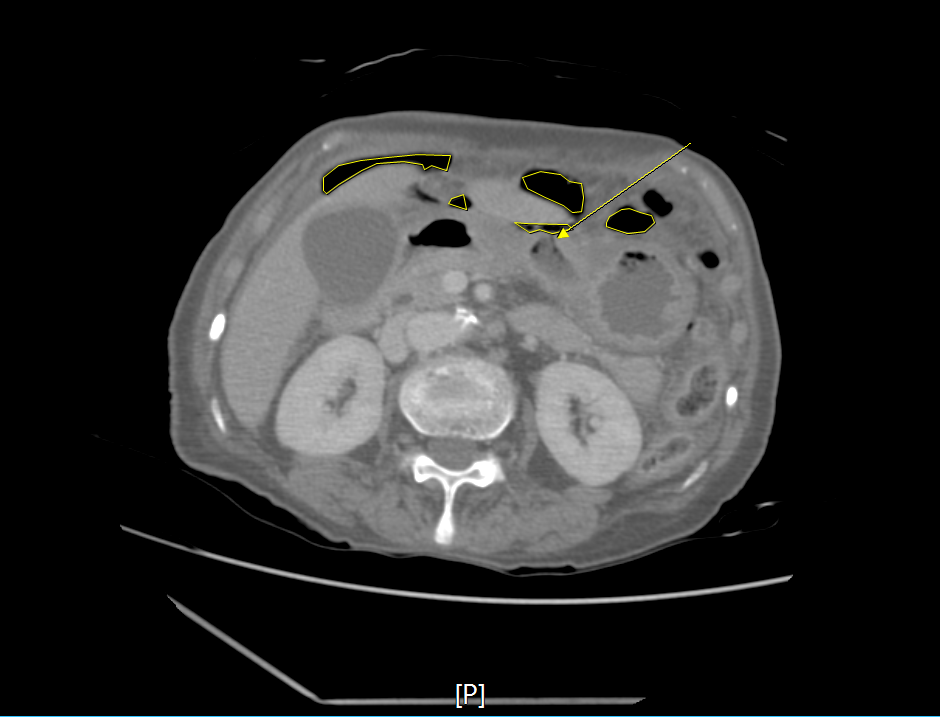

CT에서는 prehepatic area(간앞쪽으로)로 free-air(공기음영)가 보이는 상태였다.

위장(stomach)주변으로도 free-air가 많이 보이는 상태였다.

HU**를 조정하여 다시 확인해보면, free-air와 bowel 안쪽 공기음영을 확인할 수 있다.

그리고 장벽(bowel wall)의 경계를 확인할 수 있다.

HU을 조정한 이후 stomach wall 아래 앞쪽으로 구멍이 난 것을 확인할 수 있으며, 그 주변부를 기점으로 free-air가 많이 분포하고 있음을 알 수 있다.